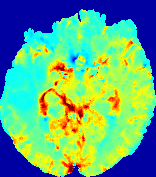

LesionRefer to captionRefer to captionRefer to captionRefer to captionRefer to captionRefer to caption𝐕rgbsubscript𝐕𝑟𝑔𝑏{\bf{V}}_{rgb}Refer to captionRefer to captionRefer to captionRefer to captionRefer to captionRefer to caption𝐕2subscriptnorm𝐕2{\|\bf{V}}\|_{2}Refer to captionRefer to captionRefer to captionRefer to captionRefer to captionRefer to captionRefer to caption3.53.53.52.82.82.82.12.12.11.41.41.40.70.70.70.00.00.0(mm/s)𝑚𝑚𝑠(mm/s)D𝐷DRefer to captionRefer to captionRefer to captionRefer to captionRefer to captionRefer to captionRefer to caption0.0200.0200.0200.0160.0160.0160.0120.0120.0120.0080.0080.0080.0040.0040.0040.0000.0000.000(mm2/s)𝑚superscript𝑚2𝑠(mm^{2}/s)Slice #1Slice #2Slice #3Slice #4Slice #5Slice #6

Figure 3: PIANO feature maps for one stroke patient, where the lesion is located in the left hemisphere. Top row: segmented stroke lesion region (white) on different slices, obtained from ISLES 2017. The corresponding slices for the PIANO feature maps are shown in the following rows.

For a better insight into an estimated velocity field 𝐕𝐕{\bf{V}} and diffusion field 𝐃𝐃{\bf{D}}, we compute the following maps: (1) 𝐕rgbsubscript𝐕𝑟𝑔𝑏{\bf{V}}_{rgb}: Color-coded orientation map of 𝐕=(Vx,Vy,Vz)T𝐕superscriptsuperscript𝑉𝑥superscript𝑉𝑦superscript𝑉𝑧𝑇{\bf{V}}=(V^{x},V^{y},V^{z})^{T}, obtained by normalizing 𝐕𝐕{\bf{V}} to unit length and mapping its 3 components to red, green, blue respectively; (2) 𝐕2subscriptnorm𝐕2\|{\bf{V}}\|_{2}: 222 norm of 𝐕𝐕{\bf{V}}; (3) D𝐷D: scalar field in Eq. 5.

Fig. 3 and Fig. 4 show the PIANO feature maps estimated from two ISLES 2017 patients: all are highly consistent with the lesion in both cases. Details of the blood flow trajectories are revealed in 𝐕rgbsubscript𝐕𝑟𝑔𝑏{\bf{V}}_{rgb} by the ridged patterns and the sharp changes of colors in the unaffected (right) hemisphere, while the flat patterns appearing within the lesion provide little directional information about the velocity and indicate low velocity magnitudes. Velocity magnitudes are more directly visualized via 𝐕2subscriptnorm𝐕2\|{\bf{V}}\|_{2}, from which one can easily locate the lesion where 𝐕2subscriptnorm𝐕2\|{\bf{V}}\|_{2} is low. D𝐷D also indicates lower diffusion values in the lesion, though with less contrast potentially due to the fact that it captures the accumulated effect of CA diffusion at the voxel-level.